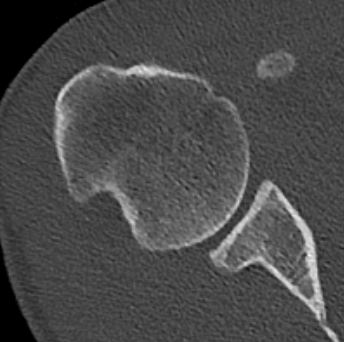

Bone block positioning

Concepts

- coracoid must not overhang medial to avoid osteoarthritis

- coracoid < 5 mm medial to glenoid rim

- coracoid lower half of glenoid 2 - 5 o'clock

- fixation screws purchases posterior glenoid cortex

- screws do not penetrate articular surface

Graft malposition

Screws and graft too medial

Bone graft too medial

Coracoid graft too superior on glenoid